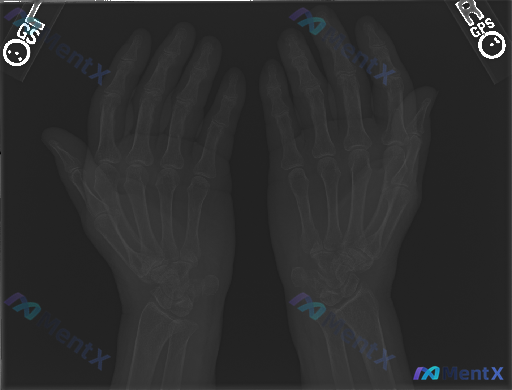

整理到一组双侧手部正位X光片的影像资料及临床背景: 影像表现 - 双侧指骨、掌骨、腕骨骨皮质连续,未见明确透亮骨折线; - 骨小梁结构尚可见,无明显局限性稀疏或异常致密增高,无明显骨质破坏或肿瘤征象; - 各掌指、指间关节对位正常,关节间隙基本对称,无明显狭窄或增宽; - 软组织轮廓清晰,未见明显肿...